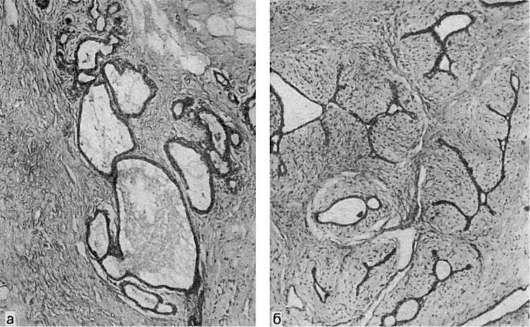

Кдоброкачественным опухолям относят фиброаденому, которая имеет вид инкапсулированного узла плотной консистенции. Характерна пролиферация альвеол и внутридольковых протоков. Соединительная ткань может обрастать внутридольковые протоки (периканаликулярная фиброаденома - рис. 108) или врастать в них(интраканаликулярная фиброаденома - см. рис. 108). Редко встречается листовидная (филлоидная) опухоль.

Рис.

108. Фиброаденома молочной железы:

а - периканаликулярная; б - интраканаликулярная